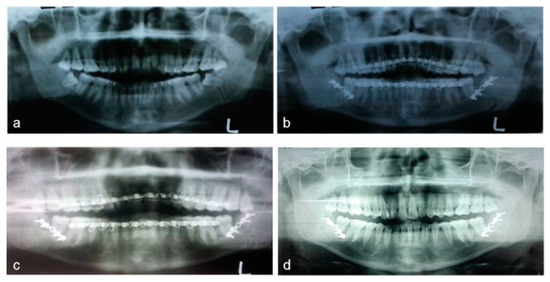

Isolated Bilateral Mandibular Angle Fractures: An Extensive Literature Review of the Rare Clinical Phenomenon with Presentation of a Classical Clinical Model

Case Report